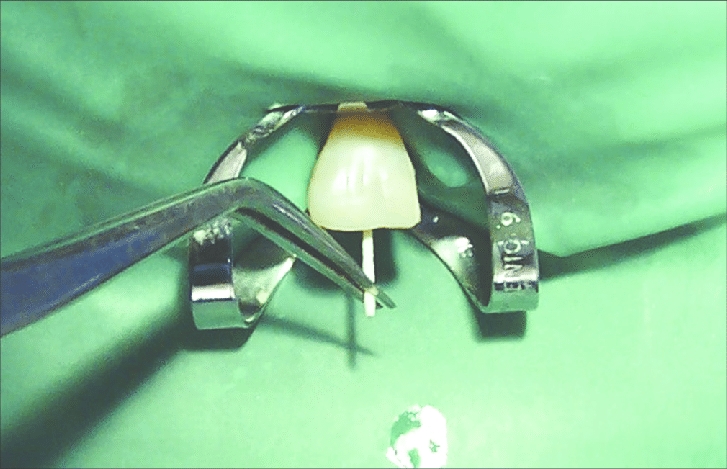

Root Canal Treatment: Diapex Plus, Diapaste, Dia-Root Bio MTA.